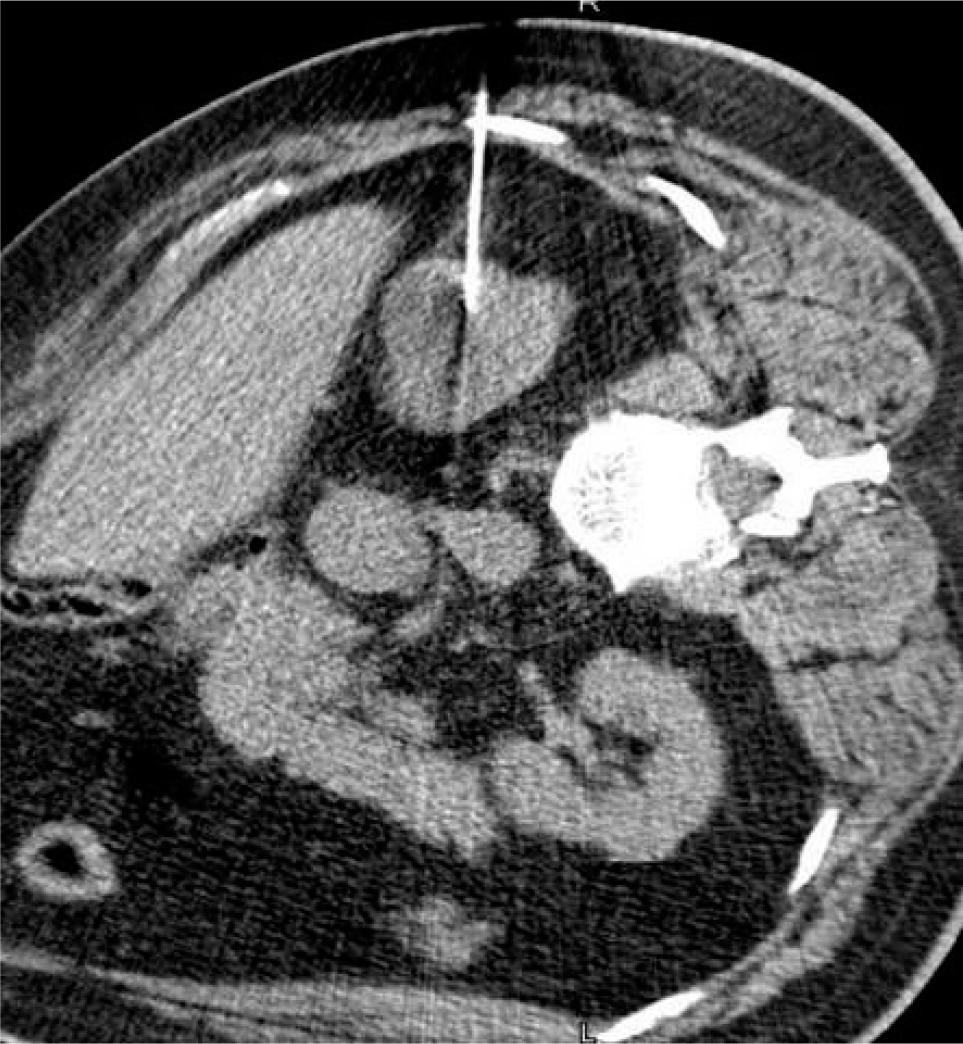

In cryoablation, the tumor is cooled to a temperature sufficient to obtain cell necrosis. Cryogen gas (typically argon) is depressurized, causing a decrease in temperature at the tip of an antenna—a phenomenon termed the Joule–Thomson effect. Through the tip of the antenna, passive thermal diffusion acts on tumor cells. Intracellular and extracellular crystals are produced by slow and fast freezing cycles (generally two), and these cycles cause cell death through cellular dehydration, vascular thrombosis, and membrane rupture (15). While −20°C is the proven temperature at which cell necrosis occurs in cryoablation, −40°C is the typical temperature achieved in real world practice. The target temperature is obtained at least 3.1 mm inside the ice ball, with shorter distances insufficient for achieving cell death (16) (Figures 1A–1C).

Figure 1: (A) Ice ball seen on the end of cryoablation probe. (B) Ice ball seen in renal tumor during cryoablation. (C) Depiction of isotherms of ice ball.